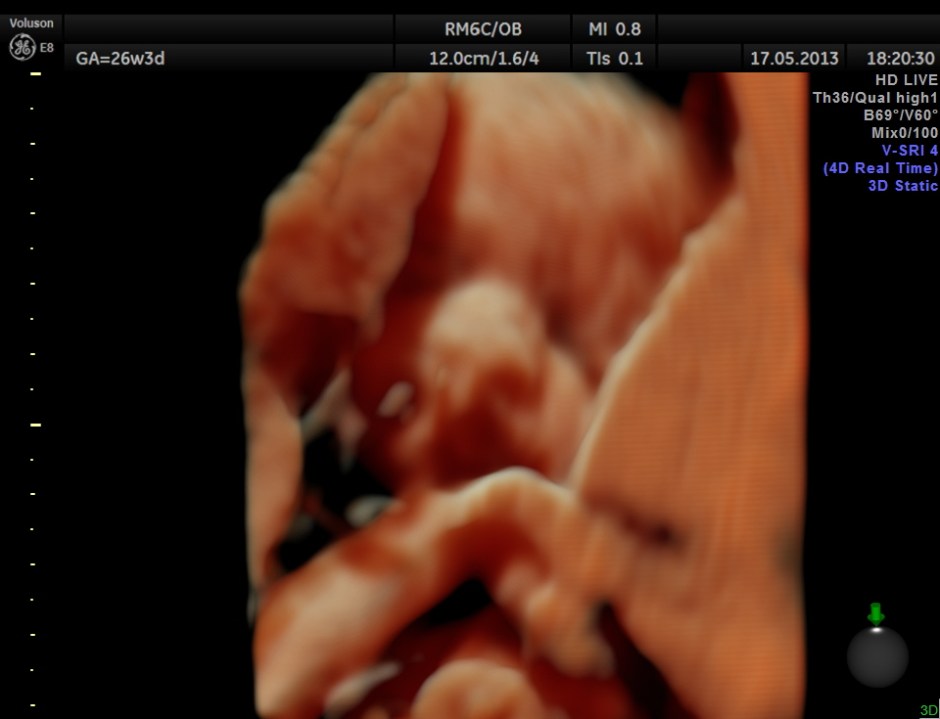

The following are 3 D reconstructed sagittal and coronal images .

The following images show the face and the palate.